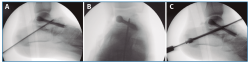

En segundo lugar, se aborda la articulación ST como indican Carranza et al.(30), se penetra la ST anterior y media por una incisión solo cutánea de 1 cm sobre el seno del tarso y la ST posterior por un portal posterolateral justo lateral al tendón de Aquiles, similar al portal artroscópico posterolateral descrito por van Dijk(31). Por estos 2 portales, finalmente se cruenta la articulación bajo control fluoroscópico hasta tejido subcondral con escoplos y brocas motorizadas (Figura 2).

Finalmente, se realiza la osteosíntesis a compresión con un tornillo (ICOS® 6,5 mm; un caso con tornillo HCS® Synthes 6,5) primero de la TN (Figura 3) y después de la ST (Figura 4)(29)(30).

Figura 2. Cruentación de la articulación subastragalina, bajo control fluoroscópico, hasta tejido subcondral, con escoplos (A) y brocas motorizadas (B y C).

Figura 3. Reducción y fijación con aguja guía de la articulación astrágalo-escafoidea bajo control fluoroscópico en lateral (A) y anteroposterior (B) y osteosíntesis a compresión con un tornillo (C; ICOS® 6,5 mm).

Figura 4. Fijación con aguja guía de la articulación subastragalina bajo control fluoroscópico en lateral (A) y anteroposterior (B) y osteosíntesis a compresión con un tornillo (C; ICOS® 6,5 mm).